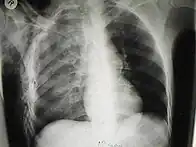

Les cas importants d'emphysème sous-cutané sont faciles à diagnostiquer en raison des signes caractéristiques de l'affection. Dans certains cas, les signes sont subtils, ce qui rend le diagnostic plus difficile. L'imagerie médicale est utilisée pour diagnostiquer la maladie ou confirmer un diagnostic établi à l'aide de signes cliniques. Sur une radiographie du thorax, l'emphysème sous-cutané peut être vu comme des stries radiotransparentes dans le modèle attendu du groupe de muscles principaux du pectoral. L'air présent dans les tissus sous-cutanés peut interférer avec la radiographie du thorax, ce qui peut masquer des affections graves comme le pneumothorax. Elle peut également réduire l'efficacité de l'échographie thoracique. D'autre part, comme l'emphysème sous-cutané peut être visible sur les radiographies du thorax avant un pneumothorax, sa présence peut être utilisée pour déduire celle de cette dernière lésion. L'emphysème sous-cutané peut également être observé sur les scanners, les poches d'air apparaissant comme des zones sombres. Le scanner est si sensible qu'il permet généralement de trouver l'endroit exact d'où l'air pénètre dans les tissus mous. En 1994, M. T. Macklin et C. C. Macklin ont publié d'autres aperçus sur la physiopathologie du syndrome de Macklin spontané survenant à la suite d'une grave crise d'asthme. La présence d'un emphysème sous-cutané chez une personne qui semble très malade et fébrile après une crise de vomissements suivie d'une douleur thoracique gauche est très évocatrice du diagnostic du syndrome de Boerhaave, qui est une urgence vitale causée par une rupture de l'œsophage distal. L'emphysème sous-cutané peut être une complication de l'insufflation de CO2 avec la chirurgie laparoscopique. Une augmentation soudaine du CO2 en fin de marée après la hausse initiale qui se produit avec l'insufflation (les 15-30 premières minutes) devrait faire suspecter un emphysème sous-cutané. Il est à noter que l'oxymétrie de pouls et la pression des voies aériennes ne varient pas dans l'emphysème sous-cutané, contrairement à l'intubation endobronchique, au capnothorax, au pneumothorax ou à l'embolie au CO2.